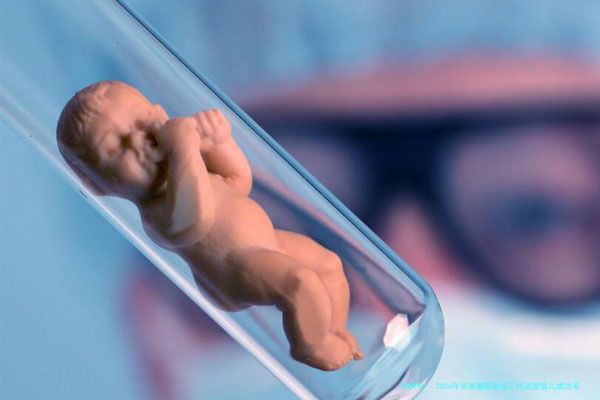

2026岁数大春哪一家医院三代试管婴儿成功率较高?在今世社会跟着经济水平的提升和生育观念的革新,三代试管婴儿技术逐渐成为许多试管助孕家庭完成生育愿望的重点途径。长春这座东北地域的璀璨明珠,一样孕育着众多三代试管婴儿医院。哪样2026年在长春,哪一家医院在为大龄夫妻进行三代试管婴儿治疗时,成功率更为优秀呢?本文将为你揭晓这一谜题。

2026年长春大龄做三代试管婴儿成功率较高的医院囊括长春小孩儿小孩综合院、长春三代试管婴儿生殖医院、长春三代试管婴儿生育专科医院、长春三代试管婴儿综合医院以及长春三代试管婴儿育医院等。这些医院仰仗其专业的设备、专业的团队和个体化的治疗计划,为大龄试管婴儿夫妻提供了还要多成功受孕的机遇。然而每位病患的情况同样是特别的,选择合适的医院和医生对三代试管婴儿成功率至关重要。因此在选择医院时,病人应综合考虑自身需求和实质情况。